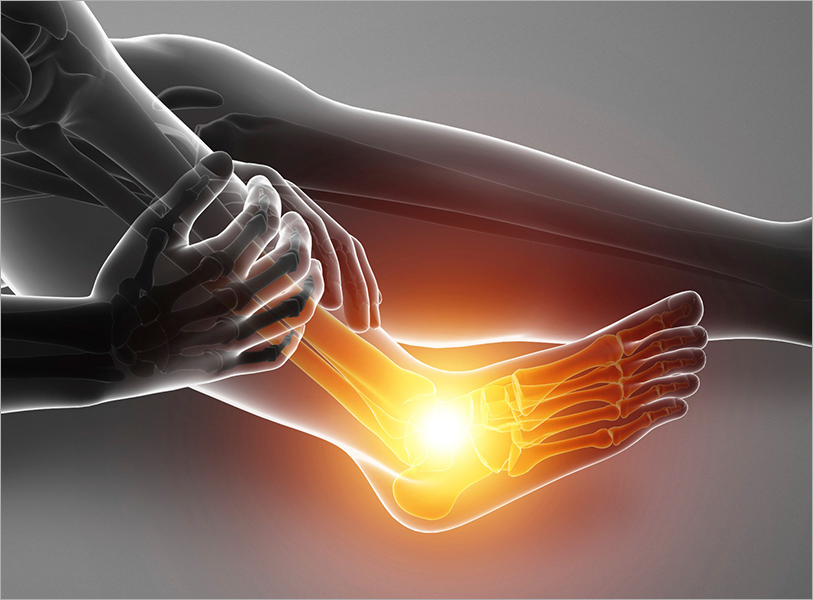

발목불안정증

발목 인대가 약해져서 올바른 역할을 하지 못하고 습관적으로 발목을 삐게 되는 질환으로,

발목 인대 손상 후 치료를 하지 않은 상태에서 빈번하게 발생 됩니다.

발목불안정증을 방치하게 될 경우 발목 염좌로 이어질 수 있으며

인대 조직까지도 손상을 입힐 수 있습니다.

발목불안정증 주요원인

습관적으로 발목이

자주 삐는 경우

인대가 약해지거나

늘어난 경우

발목불안정증 주요증상

- 작은 충격에도 쉽게 넘어지고 접질러짐

- 길을 걸을 때 발목에 힘이 거의 없이 넘어감

- 발목을 움직일 때 소리가 나고, 걸을 때마다 발목 통증